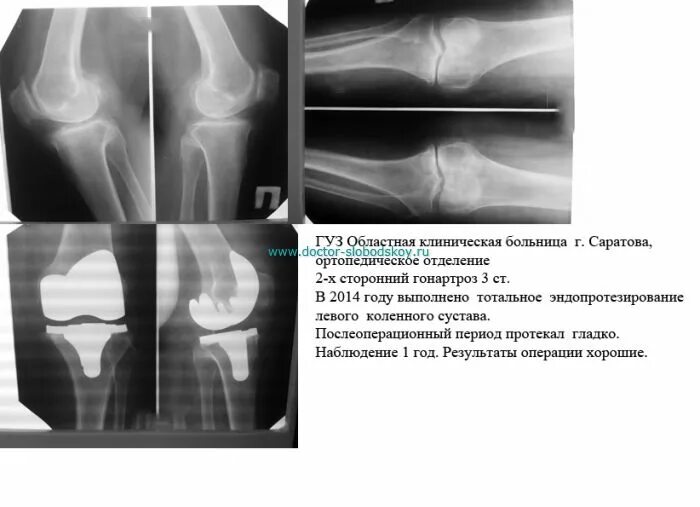

Гонартроз мрт